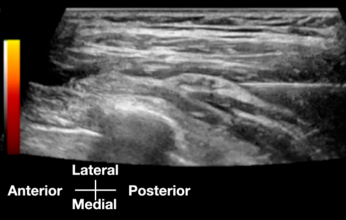

정확한 원인 지점을 찾았으면어떻게 치료해야 할까요?** 이 논문의 두 번째 핵심이 바로 여기 있습니다. 연구팀은 초음파를 보면서 장흉신경이 눌린 부위에 주사(Hydrodissection, 신경박리술)를 했는데요.

https://doi.org/10.3390/diagnostics15151891 이때, '국소 마취제(LA)'는 전혀 사용하지 않았습니다. 대신 5% 포도당 수액(D5W)을 사용했죠. 왜 그랬을까요? 만약 마취제를 쓰면, 신경이 완전히 이완되지 않았음에도 환자는 통증을 못 느끼게 됩니다. '임시방편'인 셈이죠. 연구팀은 마취제를 쓰지 않고 포도당 용액으로 신경 주변 근막을 '스르륵' 박리하는 ** 기법을 썼습니다.

말 그대로, 근막의 긴장을 이완 시켜

신경의 압박을 해소시켜 주는 것이죠.

이러한 시술 중에 환자가 직접

"어? 통증이 사라졌어요!"라고

실시간으로 피드백을 줄 수 있었고

이는 신경이 '화학적'으로 마비된 게 아니라

'물리적'으로 풀렸다는 증거가 되기도 합니다.